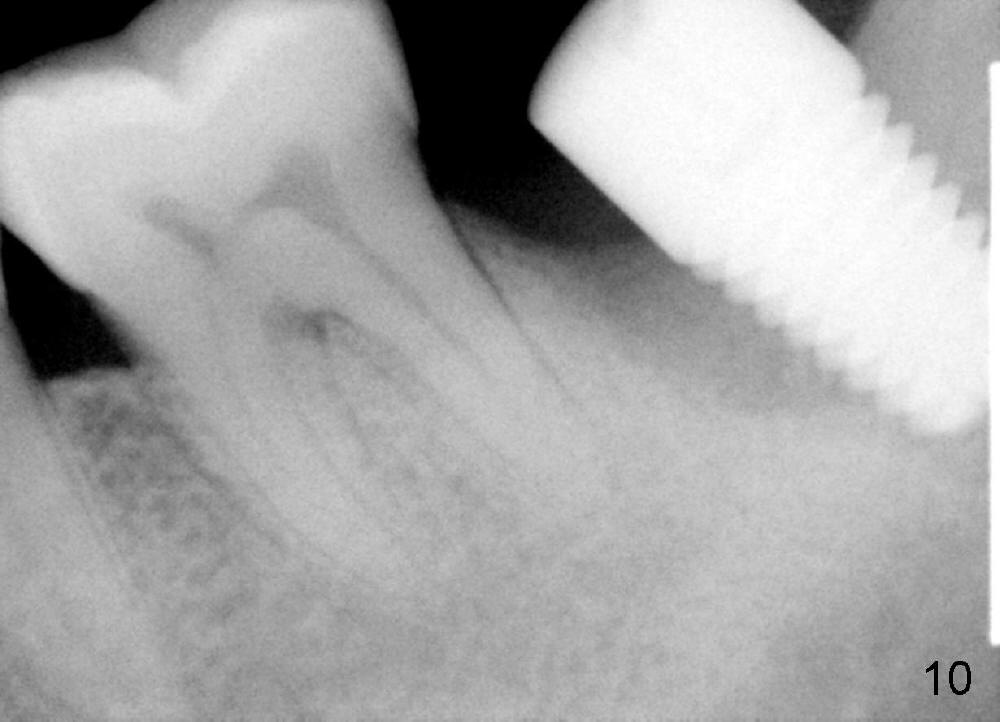

The lower left 2nd molar of a 45-year-old lady has perio-endo disease (Fig.1). The patient is not only very nervous, but also active in gag reflex. It is difficult to take good preop PA (Fig.1 *: ). Root canal therapy is performed. A relatively good PA is taken 1 year postop, again due to gap reflex (Fig.2). The tooth is still nonsalvageable (Fig.3). The last PA is taken 3.5 years before extraction and immediate implant. Infiltration anesthesia is administrated first. The patient experiences pain during early stage of osteotomy, but she does not report readily. Block anesthesia is added. Intraop PAs are taken with difficulty (Fig.4,5 with #1 sensor; 5 mm tap in place). Invasion of the inferior alveolar canal is not noted (Fig.5 dashed line). Oozing is a little more than expected. This is ignored. A 7x14 mm tapered implant is placed; the upper border of the inferior alveolar canal is not intact (Fig.6). Paresthesia area is defined next day (Fig.7). The implant is reversed for a few turns. Paresthesia area is reduced 19 days later (Fig.8). The implant is not stable. Follow up PAs are taken with difficulty (Fig.9-11). It appears that a shorter cylindrical implant is more appropriate for this case (Fig.11). The implant is stabilized with splinting with questionable result (Fig.12).